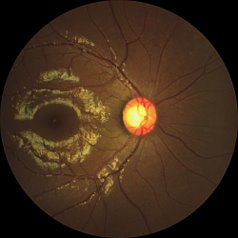

We know that diabetic retinopathy(DR) is one of the leading causes of preventable blindness. That is why we developed our own AI algorithm to automatically detect signs of DR in the retina. This makes it so much more easier to screen and refer for a DR patient.

Automatically detects signs of referable DR in under 7 seconds—fully offline, enabling rapid screening at the point of care.Structured reports with visual heatmaps highlight regions of interest, aiding patient counselling and supporting clinical referral decisions